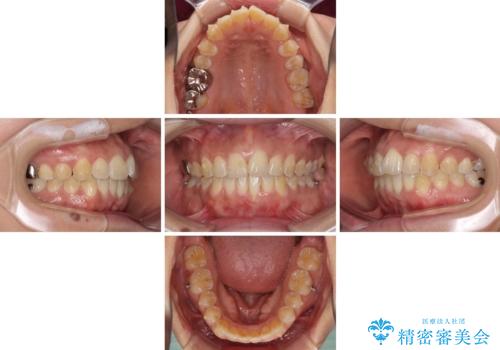

インビザラインによる狭窄歯列の拡大矯正

- 前歯のデコボコを治したいとのことで来院された患者様です。

上下顎ともに歯列全体の後方移動と側方拡大、IPR(歯と歯の間を削る)によってデコボコが解消するように設計し、インビザラインにより治療を行うこととしました。

後方移動に際し、上下の親知らずは4本とも抜歯することとしました。